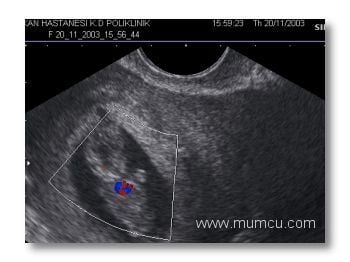

5 hafta 6 günlük gebelikte kalp atımlarının renkli doppler ile izlenmesi

Vajinal ultrasonografi